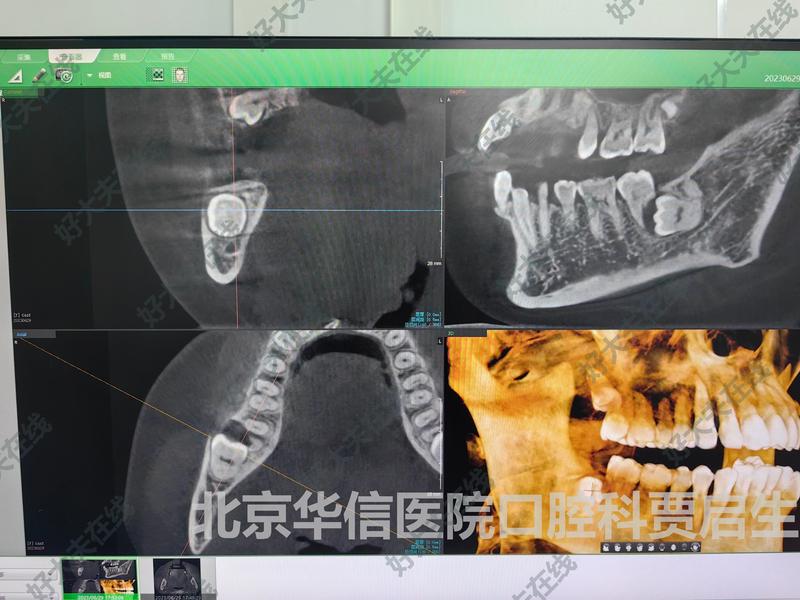

治療前 患者數(shù)年來(lái)右下后牙偶疼痛,數(shù)周來(lái)疼痛加重,來(lái)診檢查發(fā)現(xiàn)是38含牙囊腫,且導(dǎo)致37牙根吸收,需要進(jìn)行智齒拔出+37拔除術(shù)+囊腫搔刮術(shù)+植骨術(shù),屬于門診復(fù)雜病例。 治療后 治療后即刻 順利拔除37、38,并刮除囊壁,最后行植骨術(shù).

絕大多數(shù)智齒宜拔不宜留,早發(fā)現(xiàn)早診斷早拔除很有必要。有的智齒會(huì)萌出來(lái),有的不會(huì),想了解具體情況,最好結(jié)合X線片、曲面斷層片或者CBCT進(jìn)行評(píng)估。很多患者認(rèn)為自己的智齒不痛,就不用管它,其實(shí)這是一個(gè)誤區(qū)。凡是位置不正的智齒均有拔除的必要,并不能用疼不疼作為拔除標(biāo)準(zhǔn)。智齒萌出較晚,一般是十七八歲時(shí)萌出,拔出智齒并不會(huì)導(dǎo)致智商的下降,所以這一點(diǎn)也不用擔(dān)憂。阻生智齒、部分萌出的智齒、位置不正的智齒、嚴(yán)重齲壞的智齒、埋伏的智齒等均需要拔除。如果不確定,最好找??拼蠓驒z查確診,免得造成不必要的損害。以下是兩個(gè)案例,大家可以參考一下:總之,大家要注意自己是否長(zhǎng)了智齒,自己的智齒需不需要拔除,需要的話一定不要拖延,拔牙講究方式方法,根據(jù)我自己的經(jīng)驗(yàn),簡(jiǎn)單智齒拔除一般幾分鐘到十來(lái)分鐘,復(fù)雜的半小時(shí)內(nèi)基本都能搞定,術(shù)后遵醫(yī)囑好好養(yǎng)病,并沒(méi)有想想的痛苦,很快就會(huì)愈合。所以,鼓起勇氣,來(lái)拔智齒吧。